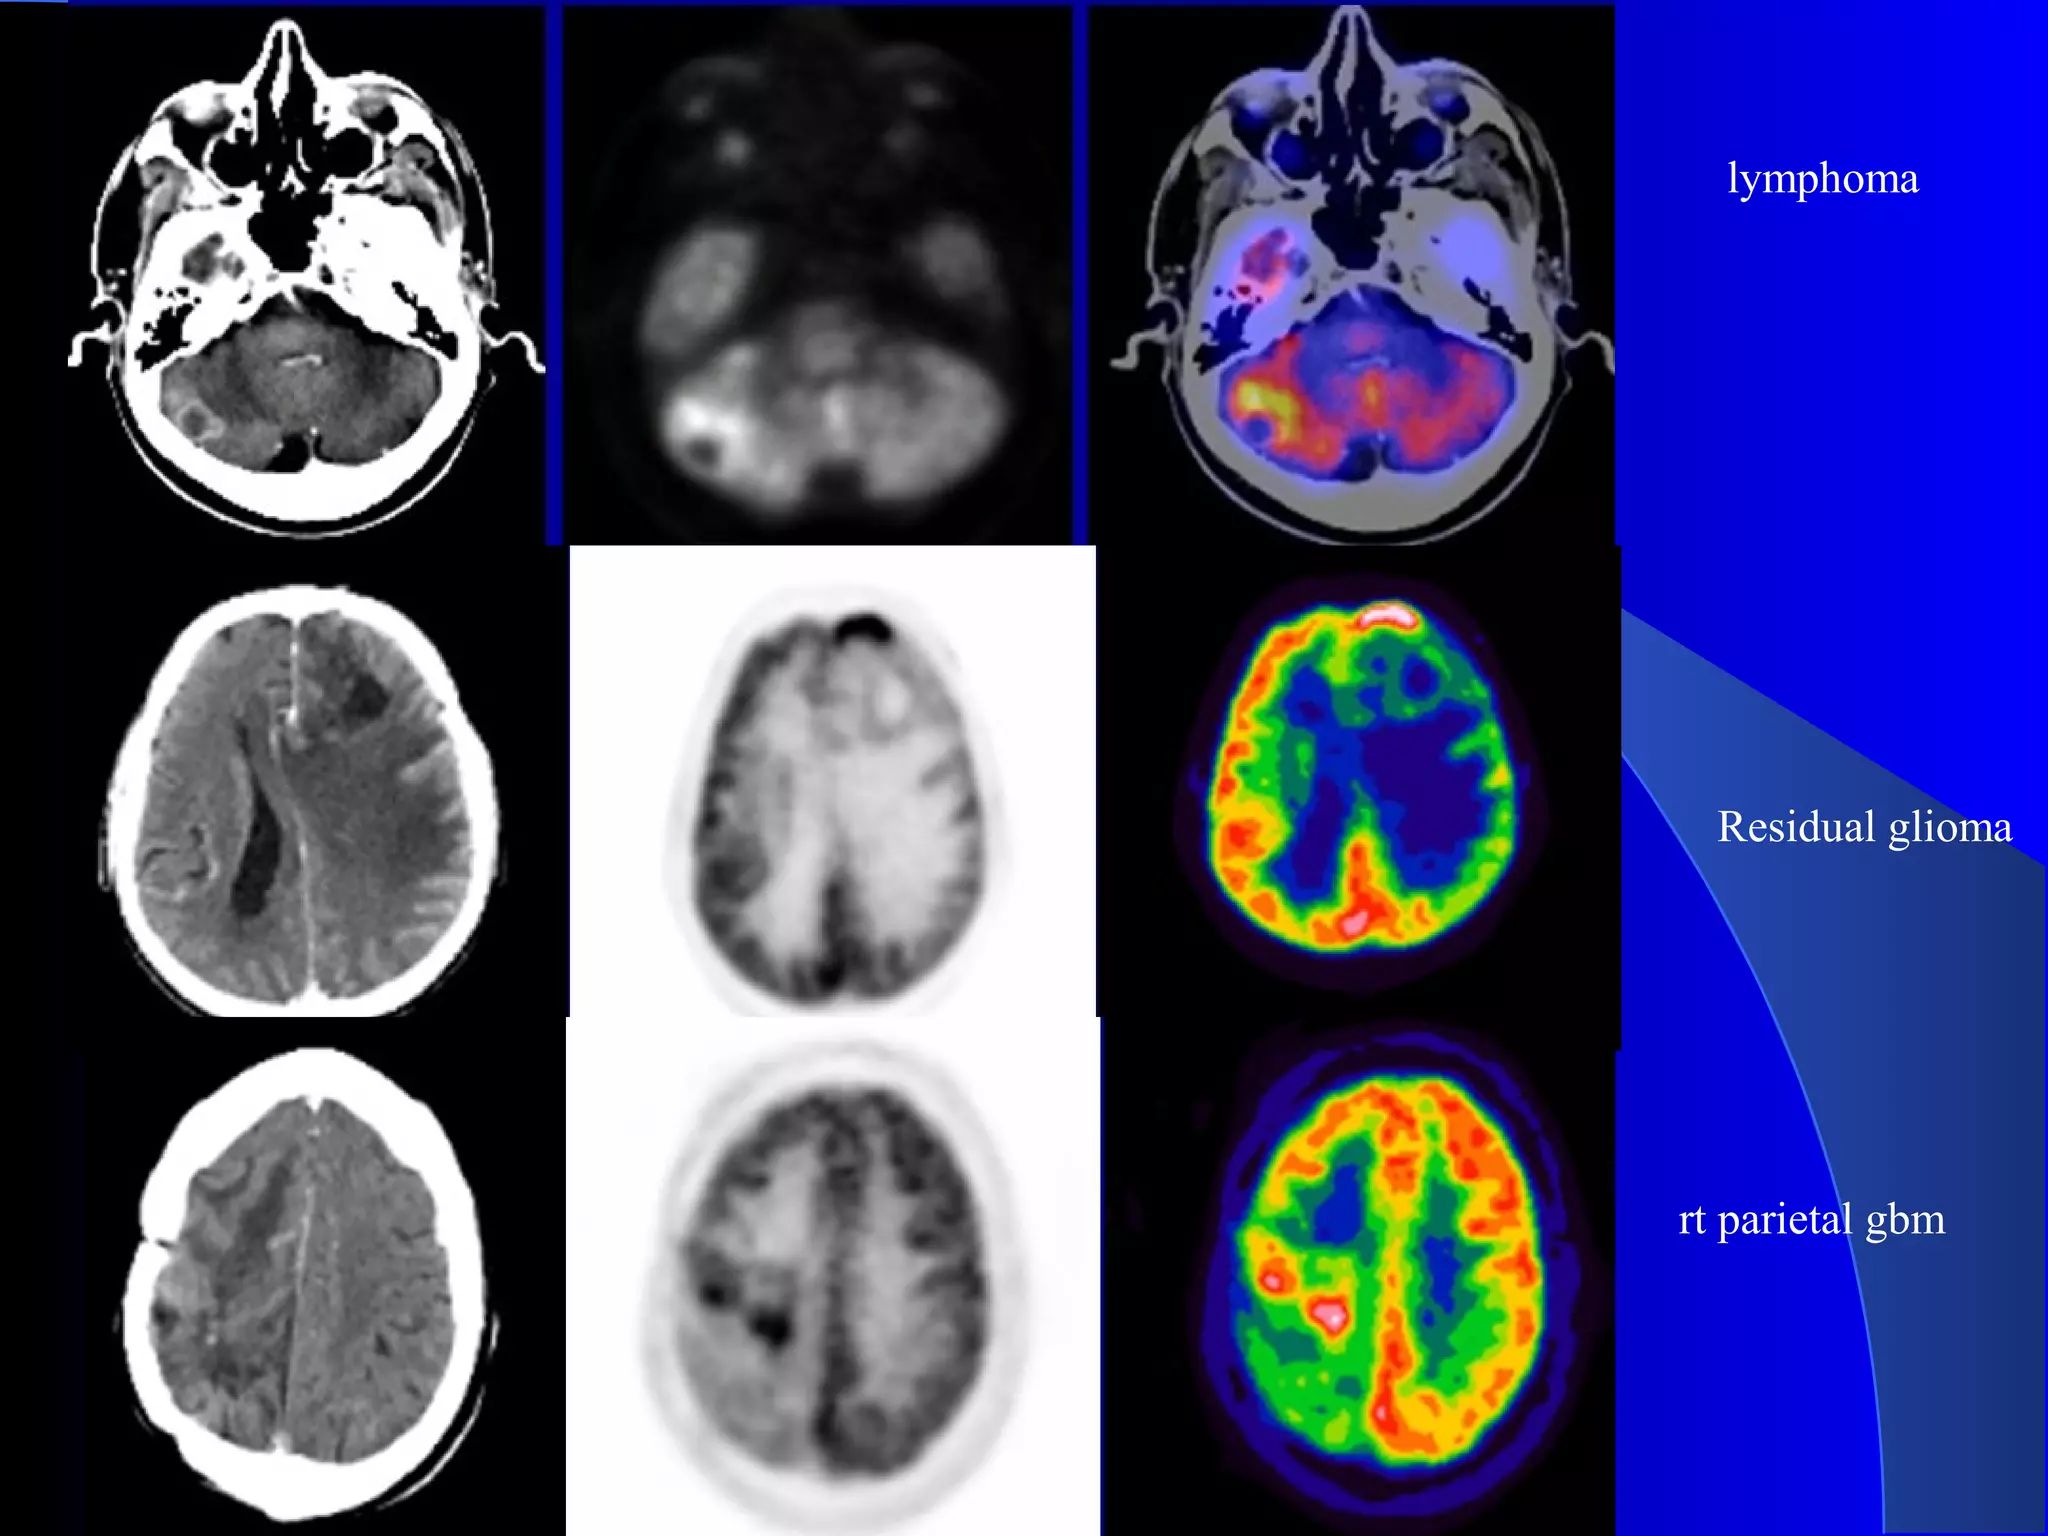

lymphoma

Residual glioma

rt parietal gbm